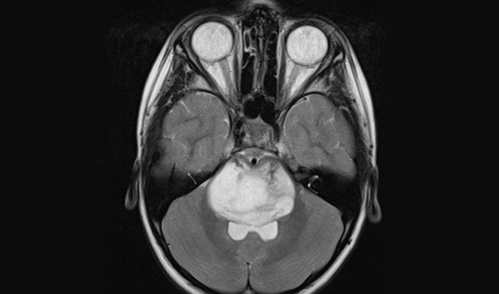

MRI of a diffuse midline glioma

Credit: Case courtesy of Dr. Jeremy Jones, radiopaedia.org. From the case rID: 68487